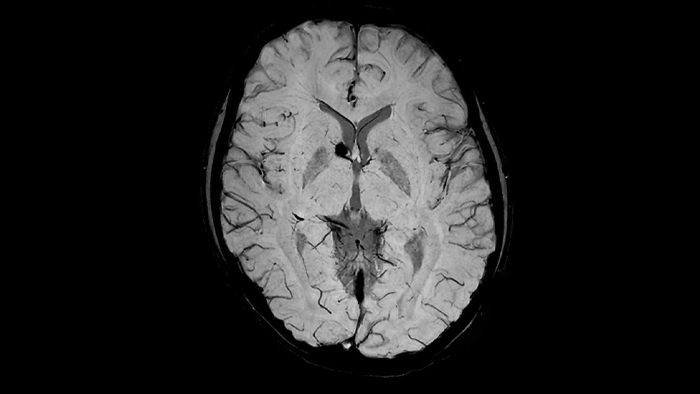

Brain

Kumamoto University Hospital, Japan

2015